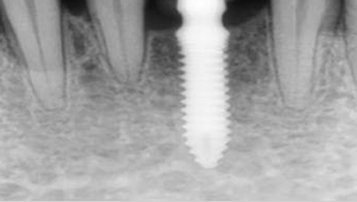

3단계: 임플란트 식립

임플란트와 발치소켓 사이 여유공간

임플란트 식립

잇몸뼈가 형성되면 임플란트를 식립합니다.